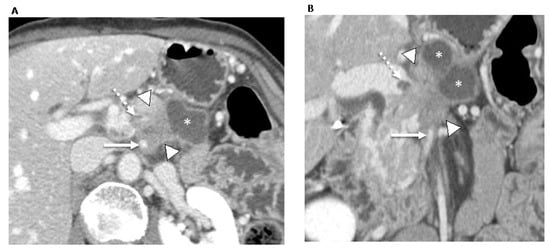

- Rigiroli, F.; Hoye, J.; Lerebours, R.; Lafata, K.J.; Li, C.; Meyer, M.; Lyu, P.; Ding, Y.; Schwartz, F.R.; Mettu, N.B.; et al. CT Radiomic Features of Superior Mesenteric Artery Involvement in Pancreatic Ductal Adenocarcinoma: A Pilot Study. Radiology 2021, 301, 610–622. [Google Scholar] [CrossRef]

| Rigiroli et al. [49], 2021 (U.S.) | 194 | -Chemo -CRT | Resectability status based on NCCN criteria | Semi-automatic, 3D VOIs containing the tumor and perivascular tissue surrounding the SMA | Python | -The model containing five perivessel and tumor radiomic features had an AUC of 0.71 to determine tumor involvement of the SMA, whereas resectability status based on NCCN criteria had an AUC of 0.54. |